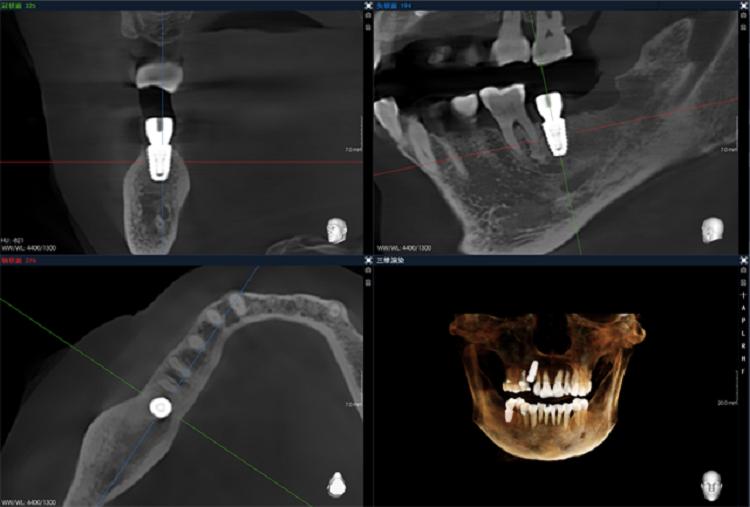

全新一代Bon準能譜偽影校正技術,去偽存真,種植體影像更清晰。

博爵1040CBCT采用高品質超大尺寸非晶硅探測器,單圈掃描360度非拼接最大一次成像視野20x14cm,單次掃描可獲取患者全口牙齒影像,雙側顳頜關節(jié),副鼻竇,鼻骨,顴骨,額骨等,穿顴穿翼等視野要求較大的復雜種植手術輕松應對,滿足正畸科,頜面外科,種植科等全科室診療需求。